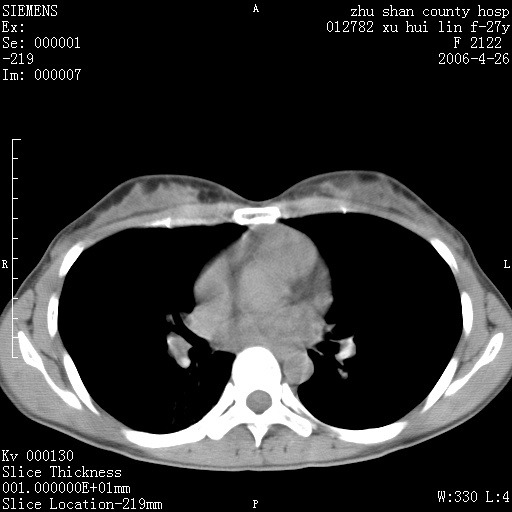

女性 病人 27岁!本院职工家属,五月前因感冒透视发现病变,ct示:左肺下叶背段感染性病变。经过半月规范抗生素治疗后复查病变无明显变化,后行四月规范抗痨治疗,复查无明显变化,后复查无效!请大家帮忙看看!

右肺下叶背段见片状高密度区,边界不清,密度不均,无钙化及空洞影,背段支气管通畅。所见层面肺门及纵隔内未见明显肿大淋巴结影。

女性 病人 27岁!本院职工家属,五月前因感冒透视发现病变,ct示:左肺下叶背段感染性病变。经过半月规范抗生素治疗后复查病变无明显变化,后行四月规范抗痨治疗,复查无明显变化,后复查无效!

诊断:首先还是考虑为慢性炎症。

机化性肺炎

从战友提供的ct图象及定位图象看应该是间质性炎症改变.如果患者不放心可建议她行纤支镜检查.